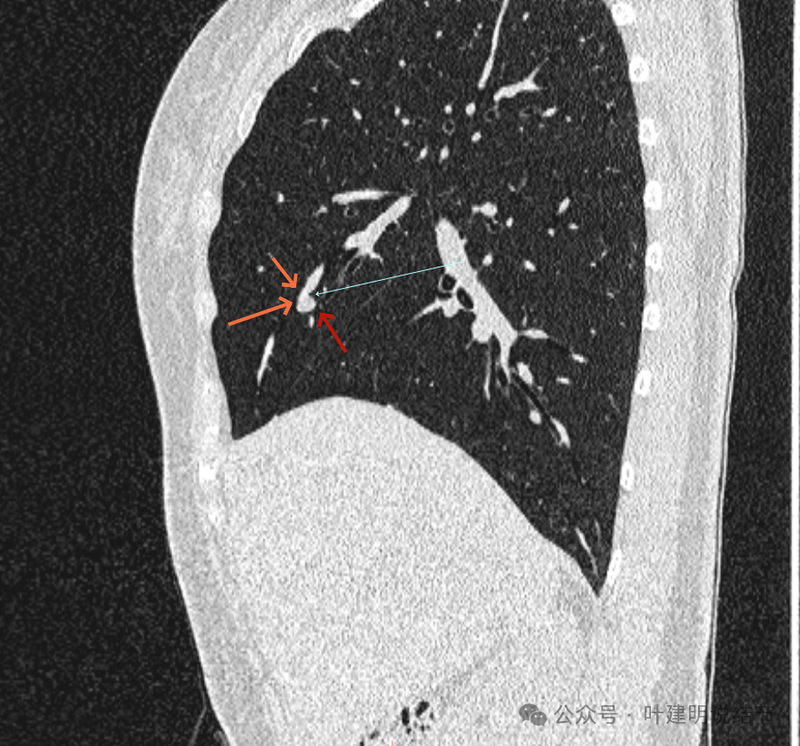

再看矢状位影像:

桔色的是血管,红色的是病灶,两者之间有间隙仍用天蓝色细线标注。

紧挨但仍有缝隙的。

血管贴着病灶,病灶表面略有毛糙之处。

血管有形成轻微血管弯征,两者紧贴。

两支血管夹着病灶,密度不同,有低密度间隙。

病灶与两侧血管关系均密切,明显觉得密度是不一样的,血管的密度略高,结节的略低。

病赤与血管在蓝色箭头处失去间隙,像是侵蚀血管壁,造成血管受侵犯破坏。病灶是软组织密度的,而且整体看有膨胀感。

病灶密度稍不均。表面不光滑。

病灶与边上血管间隙不清。

桔色箭头所示的血管受压稍有移位。

密度不同,关系密切。

边缘区域也是有膨胀感。

血管与病灶脱开后的样子。

边缘区也是基本上实性的。